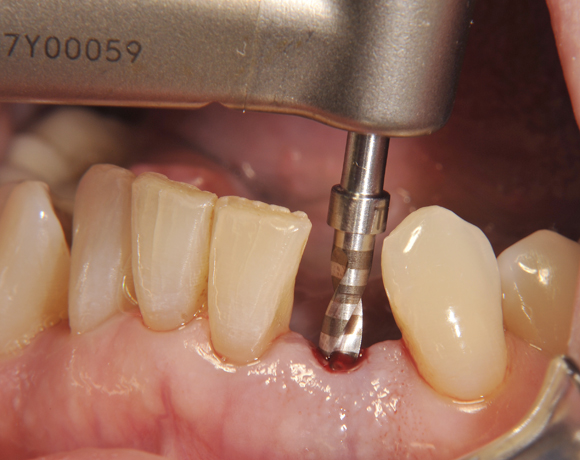

Am Beispiel dieses Patientenfalls wird gezeigt wie ein Einzelimplantat für den Unterkieferfrontzahn 33 eingesetzt wird.